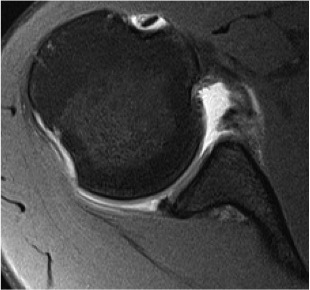

Best fit circle measurement

Best fit circle over inferior glenoid

- perpendicular line through center of circle

- measure percentage bone loss